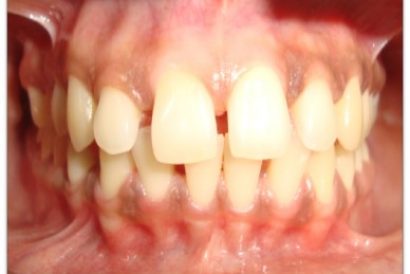

Patient Name:Padma Harkar

Tooth Involved : 11 12 13 21 22 23

Diagnosis : Fluorosis

Treatment : Direct Composite Veneers

Restoration: Direct Composite Using Nanohybrid composite

Stains masked using IVOCLAR EMPRESS COLOUR White And Honey.